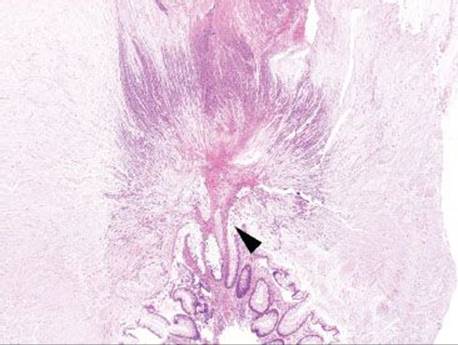

Figure 4.87 Pseudomembranous pattern. A dramatic (and beautiful) example of an eruptive pseudomembrane. The extensive fibroinflammatory debris appears to erupt from a single crypt (arrowhead).